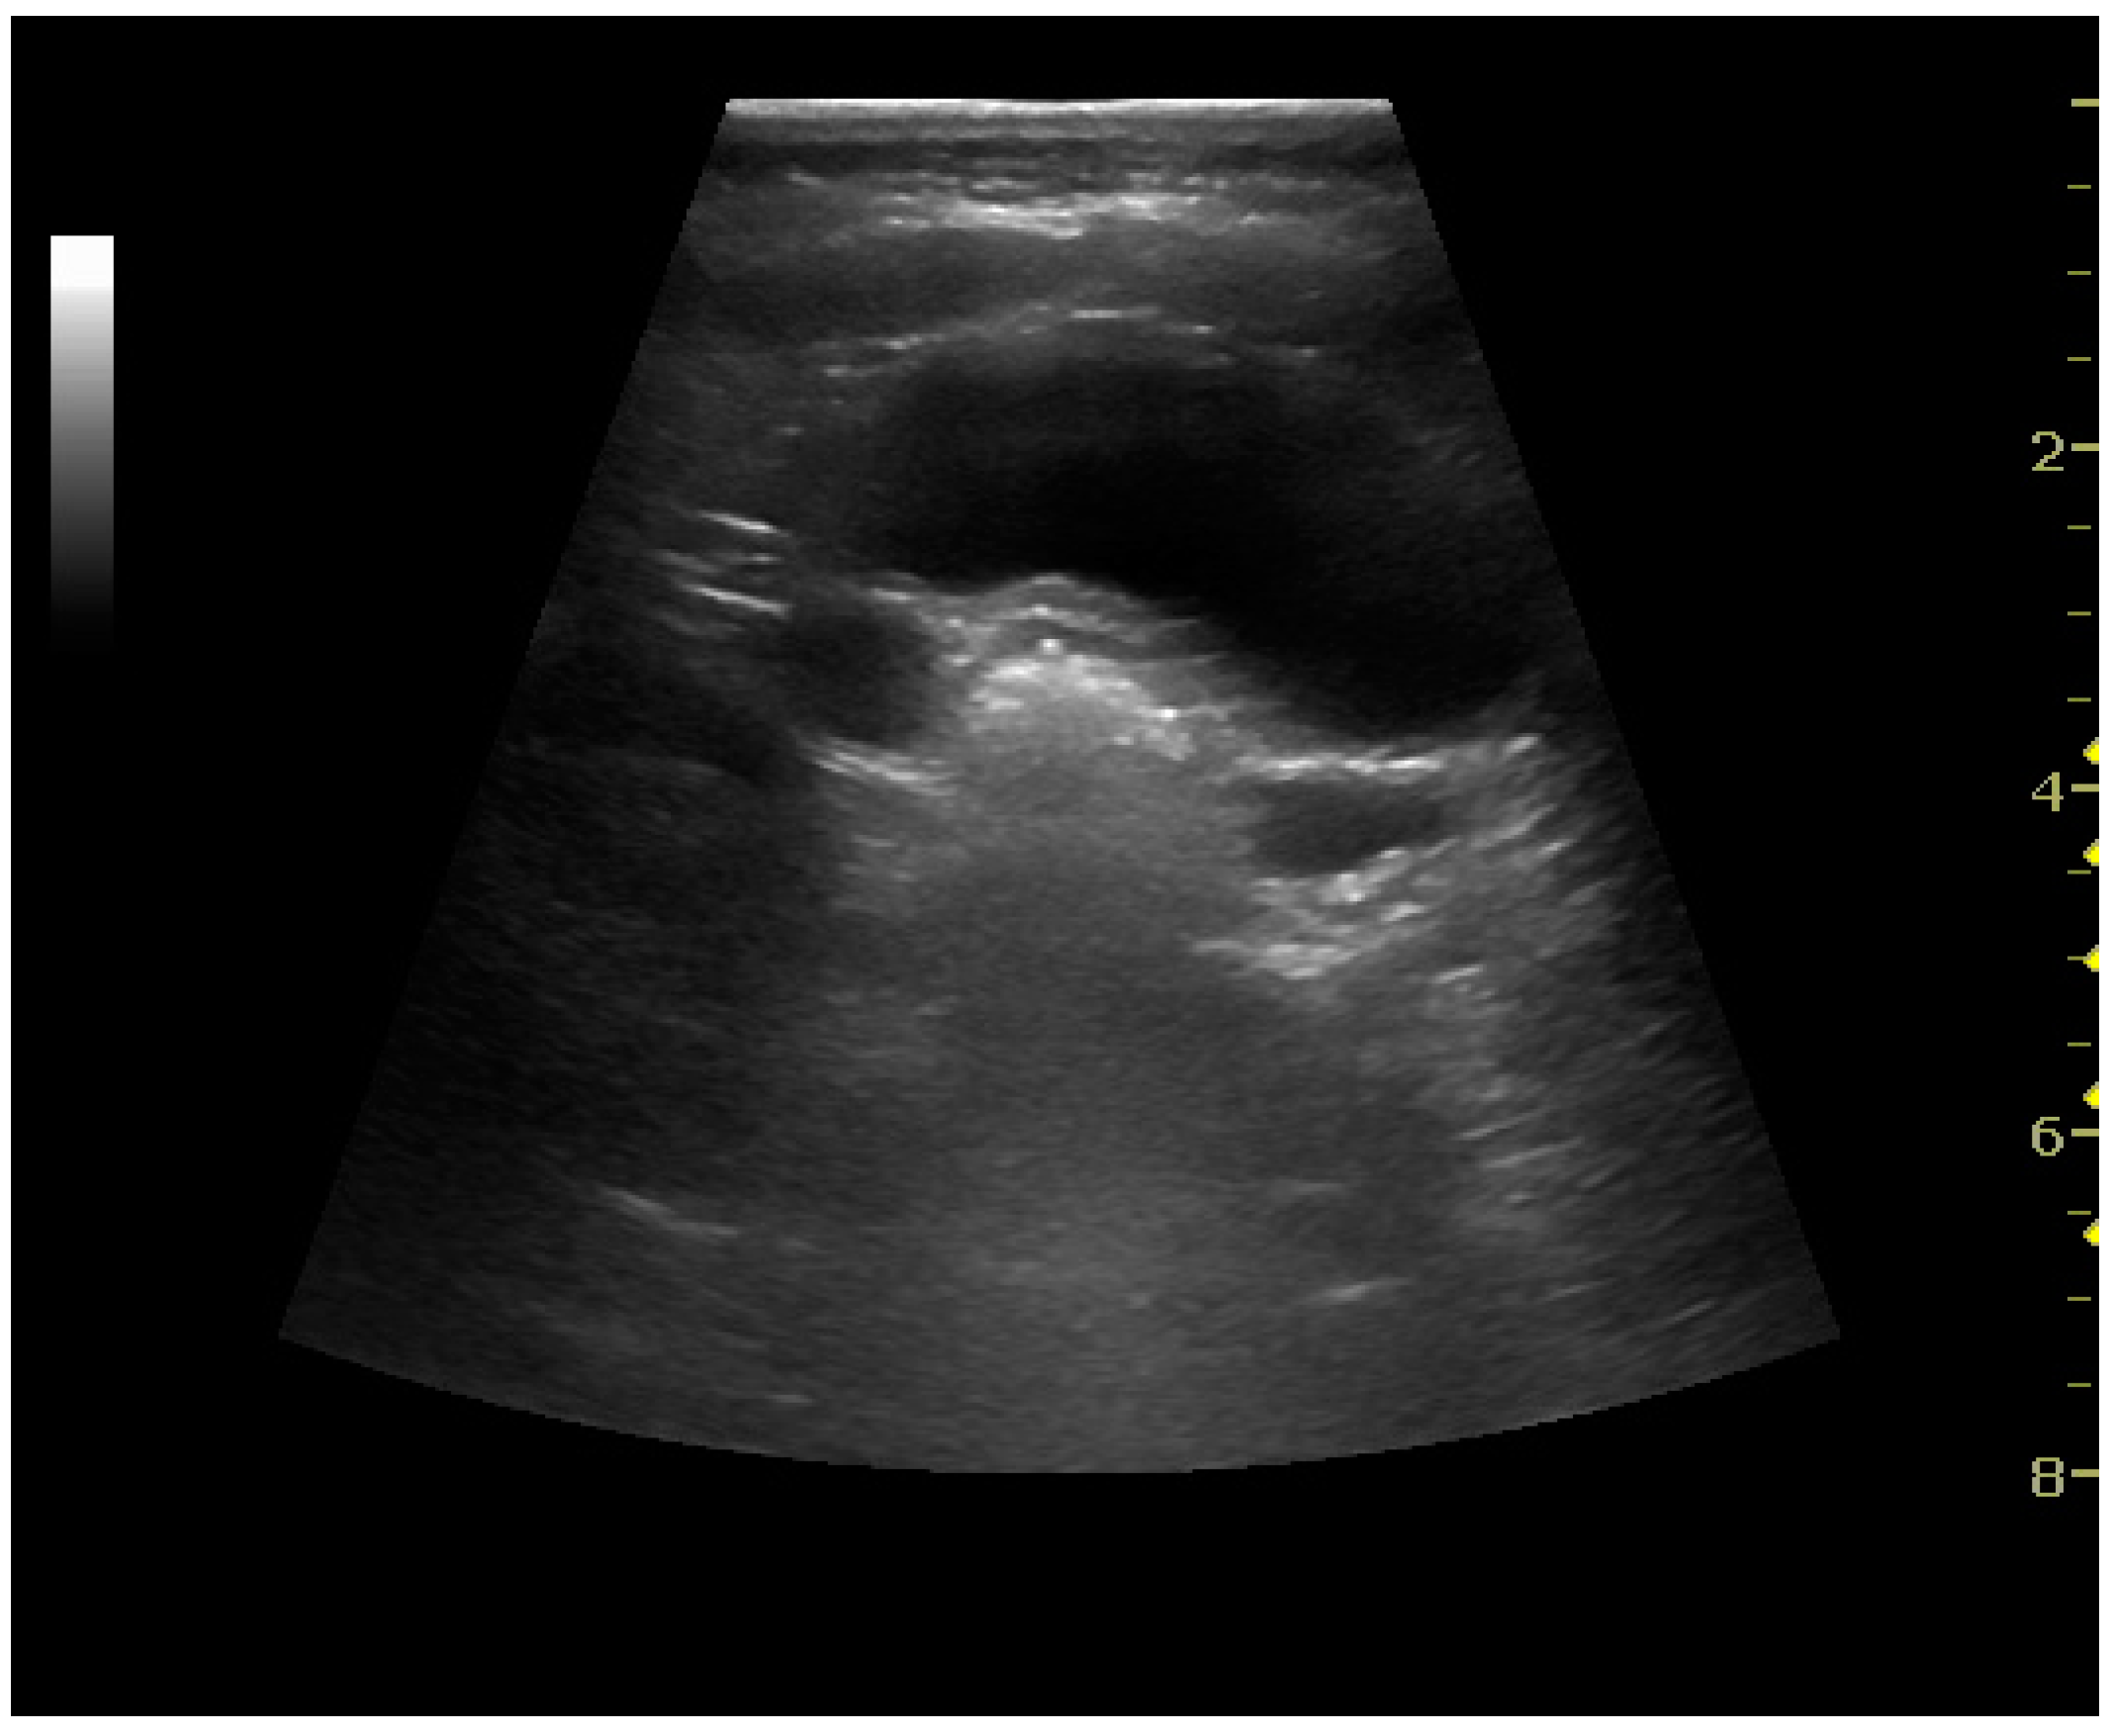

4. Cystic Renal Masses

Masses are seen as a distortion of the normal renal architecture. Most renal masses are simple cortical cysts with a round appearance and a smooth thin capsule encompassing anechoic fluid. The incidence increases with age, as at least 50% of people above the age of 50 have a simple cyst in one of the kidneys [12]. Cysts cause posterior enhancement as a consequence of reduced attenuation of the ultrasound within the cyst fluid (Figure 5). The simple cyst is a benign lesion, which does not require further evaluation [13].

Figure 5. Simple cyst with posterior enhancement in an adult kidney. Measurement of kidney length on the US image is illustrated by ‘+’ and a dashed line.